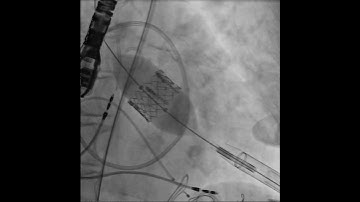

TAVR Fundamentals: Part 1